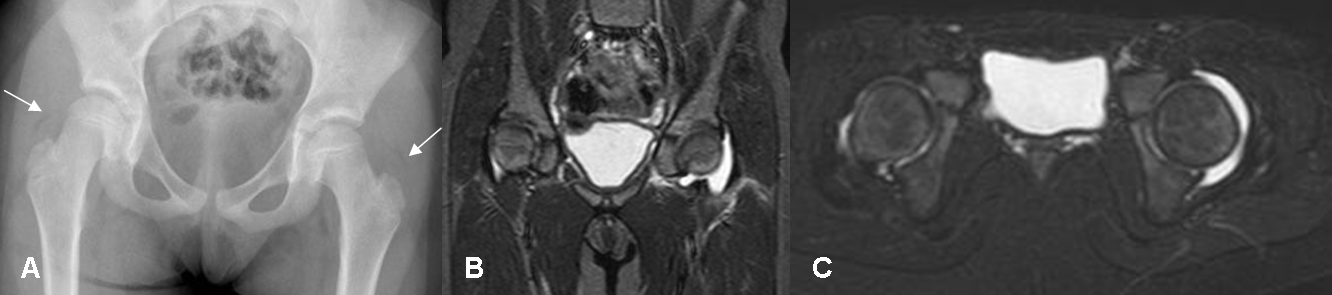

Fig 53 A. Artritis infecciosa.

A: Rx AP. Desplazamiento lateral del cojinete graso glúteo, que hace sospechar derrame articular. Lado derecho normal.

B: RM coronal y C: RM axial en STIR. Se confirma el derrame articular, por artritis infecciosa.

Posteriormente aparece osteoporosis periarticular, edema de tejidos blandos y derrame articular. La comparación con el lado contralateral o articulaciones adyacentes, pueden ayudar. (20, 21). (Fig 53 A).

En RM hay aumento del liquido articular que distiende la cápsula, hiperintenso en T2. (Fig 53 A). El líquido infectado y/o con hemartrosis, tiene una señal intermedia y heterogénea. (20).